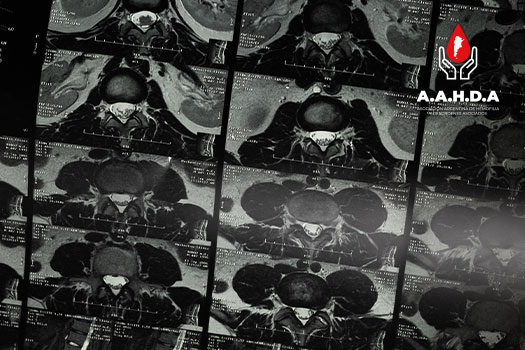

PROTOCOLOS IMÁGEN: ECOGRAFÍA

PROTOCOLOS IMÁGEN: RMI